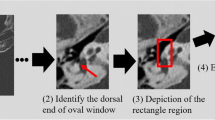

Under the supervision of radiologist B, radiologist A placed regions of interest with diameter of 1–1.5 mm on homogenous parts of the otic capsule medial to the cochlea (bone) and tympanic cavity (air) in the axial and coronal images. The locations of them were almost the same between patients. The copy-and-paste function of the region of interest was used to ensure that the location and size were identical on the DLR and HIR images. After the regions of interest had been placed, the mean of the CT attenuation for those regions and the standard deviation of the CT attenuation for air (i.e., quantitative image noise) were recorded. The contrast-to-noise ratio (CNR) was calculated using the formula

As similar to previous studies [27, 28], radiologist B placed a linear region of interest passing the handle of the malleus on axial image (Fig. 1a). The copy-and-paste function of region of interest was also used in this analysis to ensure that the location and size were identical on the DLR and HIR images. Based on the CT attenuation profile along the region of interest, the edge rise slope [29, 30] was calculated (Fig. 1b).